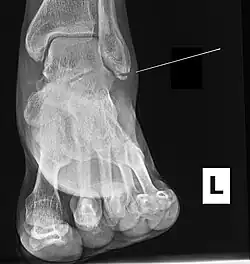

| Radiograph showing a Maisonneuve fracture of the proximal fibula | |

Ankle radiographs are used to detect widening of the tibiofibular syndesmosis or medial clear space. The medial clear space is the area between the talus of the ankle and the medial malleolus. Damage to the deltoid ligament and syndesmotic ligaments result in mortise instability, causing the talus to laterally shift and widen the medial clear space.[4][12] A clinical study, conducted in 2006 and published in the Journal of Bone and Joint Surgery, found that the medial clear space size of a normal ankle and an injured ankle measured at 4 millimetres and 5.4 millimetres in length respectively.[11] To confirm diagnosis, full-leg radiographs are used to inspect for fractures of the proximal fibula and widening of the interosseous clear space (or tibiofibular clear space). The interosseous clear space is the area between the medial side of the fibula and lateral side of the tibia. A peer-reviewed study, published in Injury in 2004, found that an interosseous clear space greater than 10 millimetres indicates diastasis of the syndesmotic ligaments.[4]

If necessary, computed tomography (CT) or magnetic resonance imaging (MRI) may also be used to clarify diagnosis. MRI scans can check for interosseous membrane or tibial tubercle damage if high instability of the ankle is diagnosed.[8][11] Arthroscopy may be used to diagnose a syndesmotic lesion but is often not recommended due to operative difficulty.[13] Stress radiographs of the ankle are used to assess the integrity of the deltoid ligament and tibiofibular syndesmosis.[9][13] The size of the medial clear space can also be measured using stress radiography.[11]

X-ray, CT, or MRI scans can be used to diagnose the extent of the Maisonneuve fracture's damage and determine whether it is a simple or comminution fracture.[8] During diagnosis, a supination-external rotation pattern of injury may also be concluded if there is an isolated fracture of the posterior tubercle of the tibia.[9]